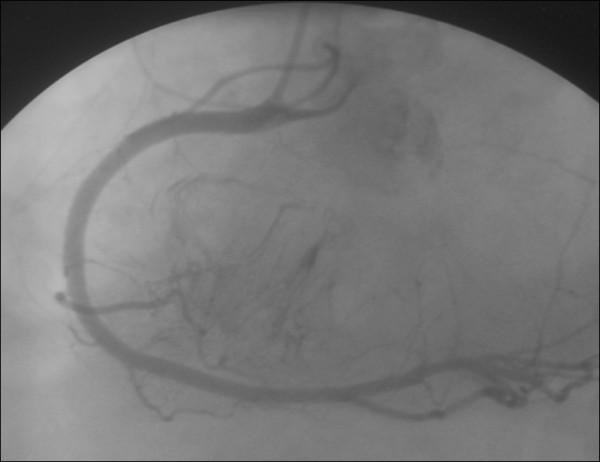

We report the case of a 64-year-old non-immunodeficient Caucasian man, with cardiac tamponade and paroxysmal third-degree atrioventricular block. Echocardiography revealed the presence of a large pericardial effusion with signs of tamponade and a right ventricular mass was suspected. Scanner investigations clarified the sites, extension and anatomic details of myocardial and pericardial infiltration. Surgical resection was performed due to the rapid impairment of his cardiac function. Analysis of the pericardial fluid and histology confirmed the diagnosis of non-Hodgkin large B-cell lymphoma. He was treated with chemotherapy.

我们报告一例64岁非免疫缺陷的白种男性病例,该患者患有心脏压塞和阵发性三度房室传导阻滞。超声心动图显示存在大量心包积液并有压塞征象,怀疑有右心室肿块。扫描检查明确了心肌和心包浸润的部位、范围及解剖细节。由于其心功能迅速恶化,遂进行了手术切除。心包液分析和组织学检查确诊为非霍奇金大B细胞淋巴瘤。他接受了化疗。